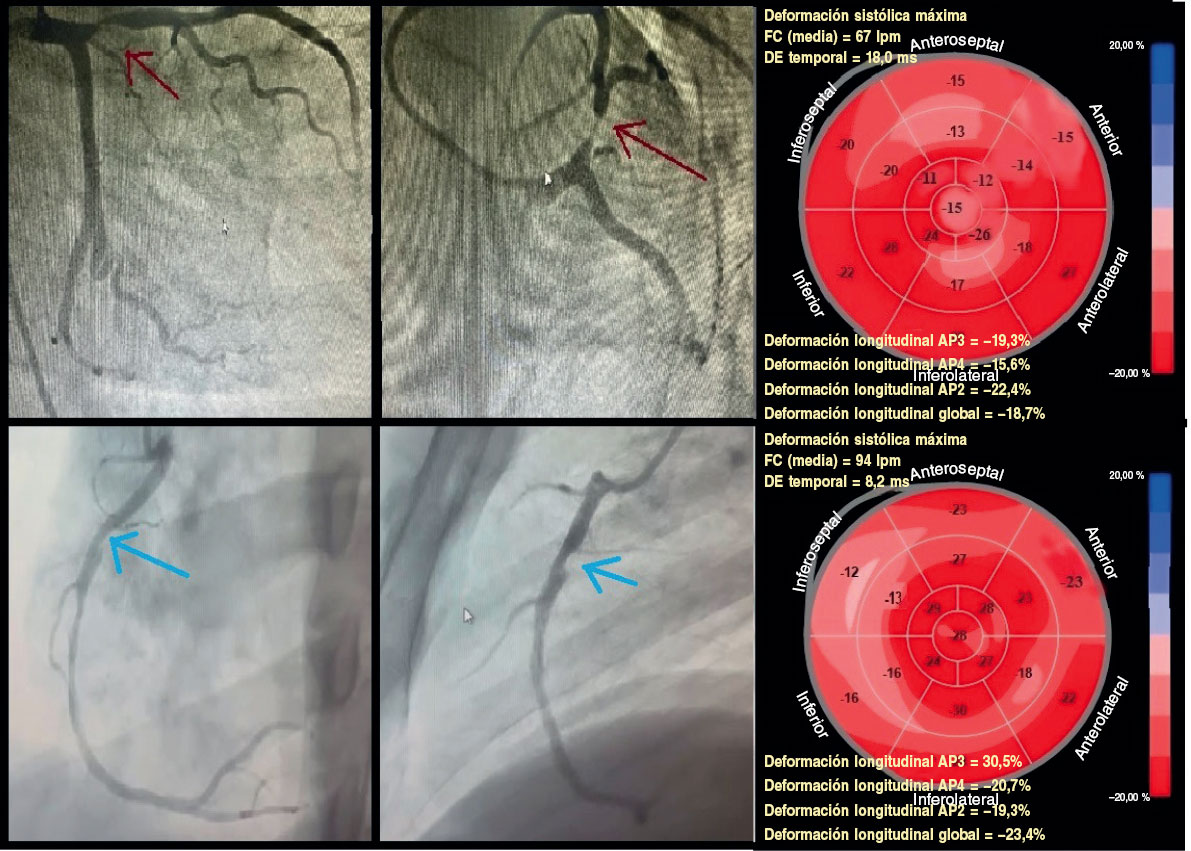

Figura 4. Deformación longitudinal territorial en participantes con cardiopatía isquémica estable. Fila superior: participante representativo del estudio con lesión proximal significativa en la descendente anterior (porcentaje de estenosis por diámetro ≥ 70%; flecha roja). La deformación longitudinal global fue del −18,7%. Siete segmentos dentro del territorio de la descendente anterior (segmentos anteroseptales, anteriores y ápex) mostraron deformación alterada (≥ −16%), lo cual corresponde a verdaderos positivos, mientras que los territorios de la circunfleja izquierda y la coronaria derecha presentaron deformación conservada (< −16%), lo cual corresponde a verdaderos negativos. Fila inferior: participante representativo del estudio con una lesión proximal significativa en la coronaria derecha (porcentaje de estenosis por diámetro ≥ 70%; flecha azul). La deformación longitudinal global fue del −23,3%. Cuatro segmentos dentro del territorio de la coronaria derecha (segmentos medio, basal inferior e inferoseptal) mostraron deformación alterada (≥ −16%), lo cual corresponde a verdaderos positivos, mientras que los territorios de la descendente anterior y la circunfleja izquierda presentaron deformación conservada (< −16%), lo cual corresponde a verdaderos negativos.